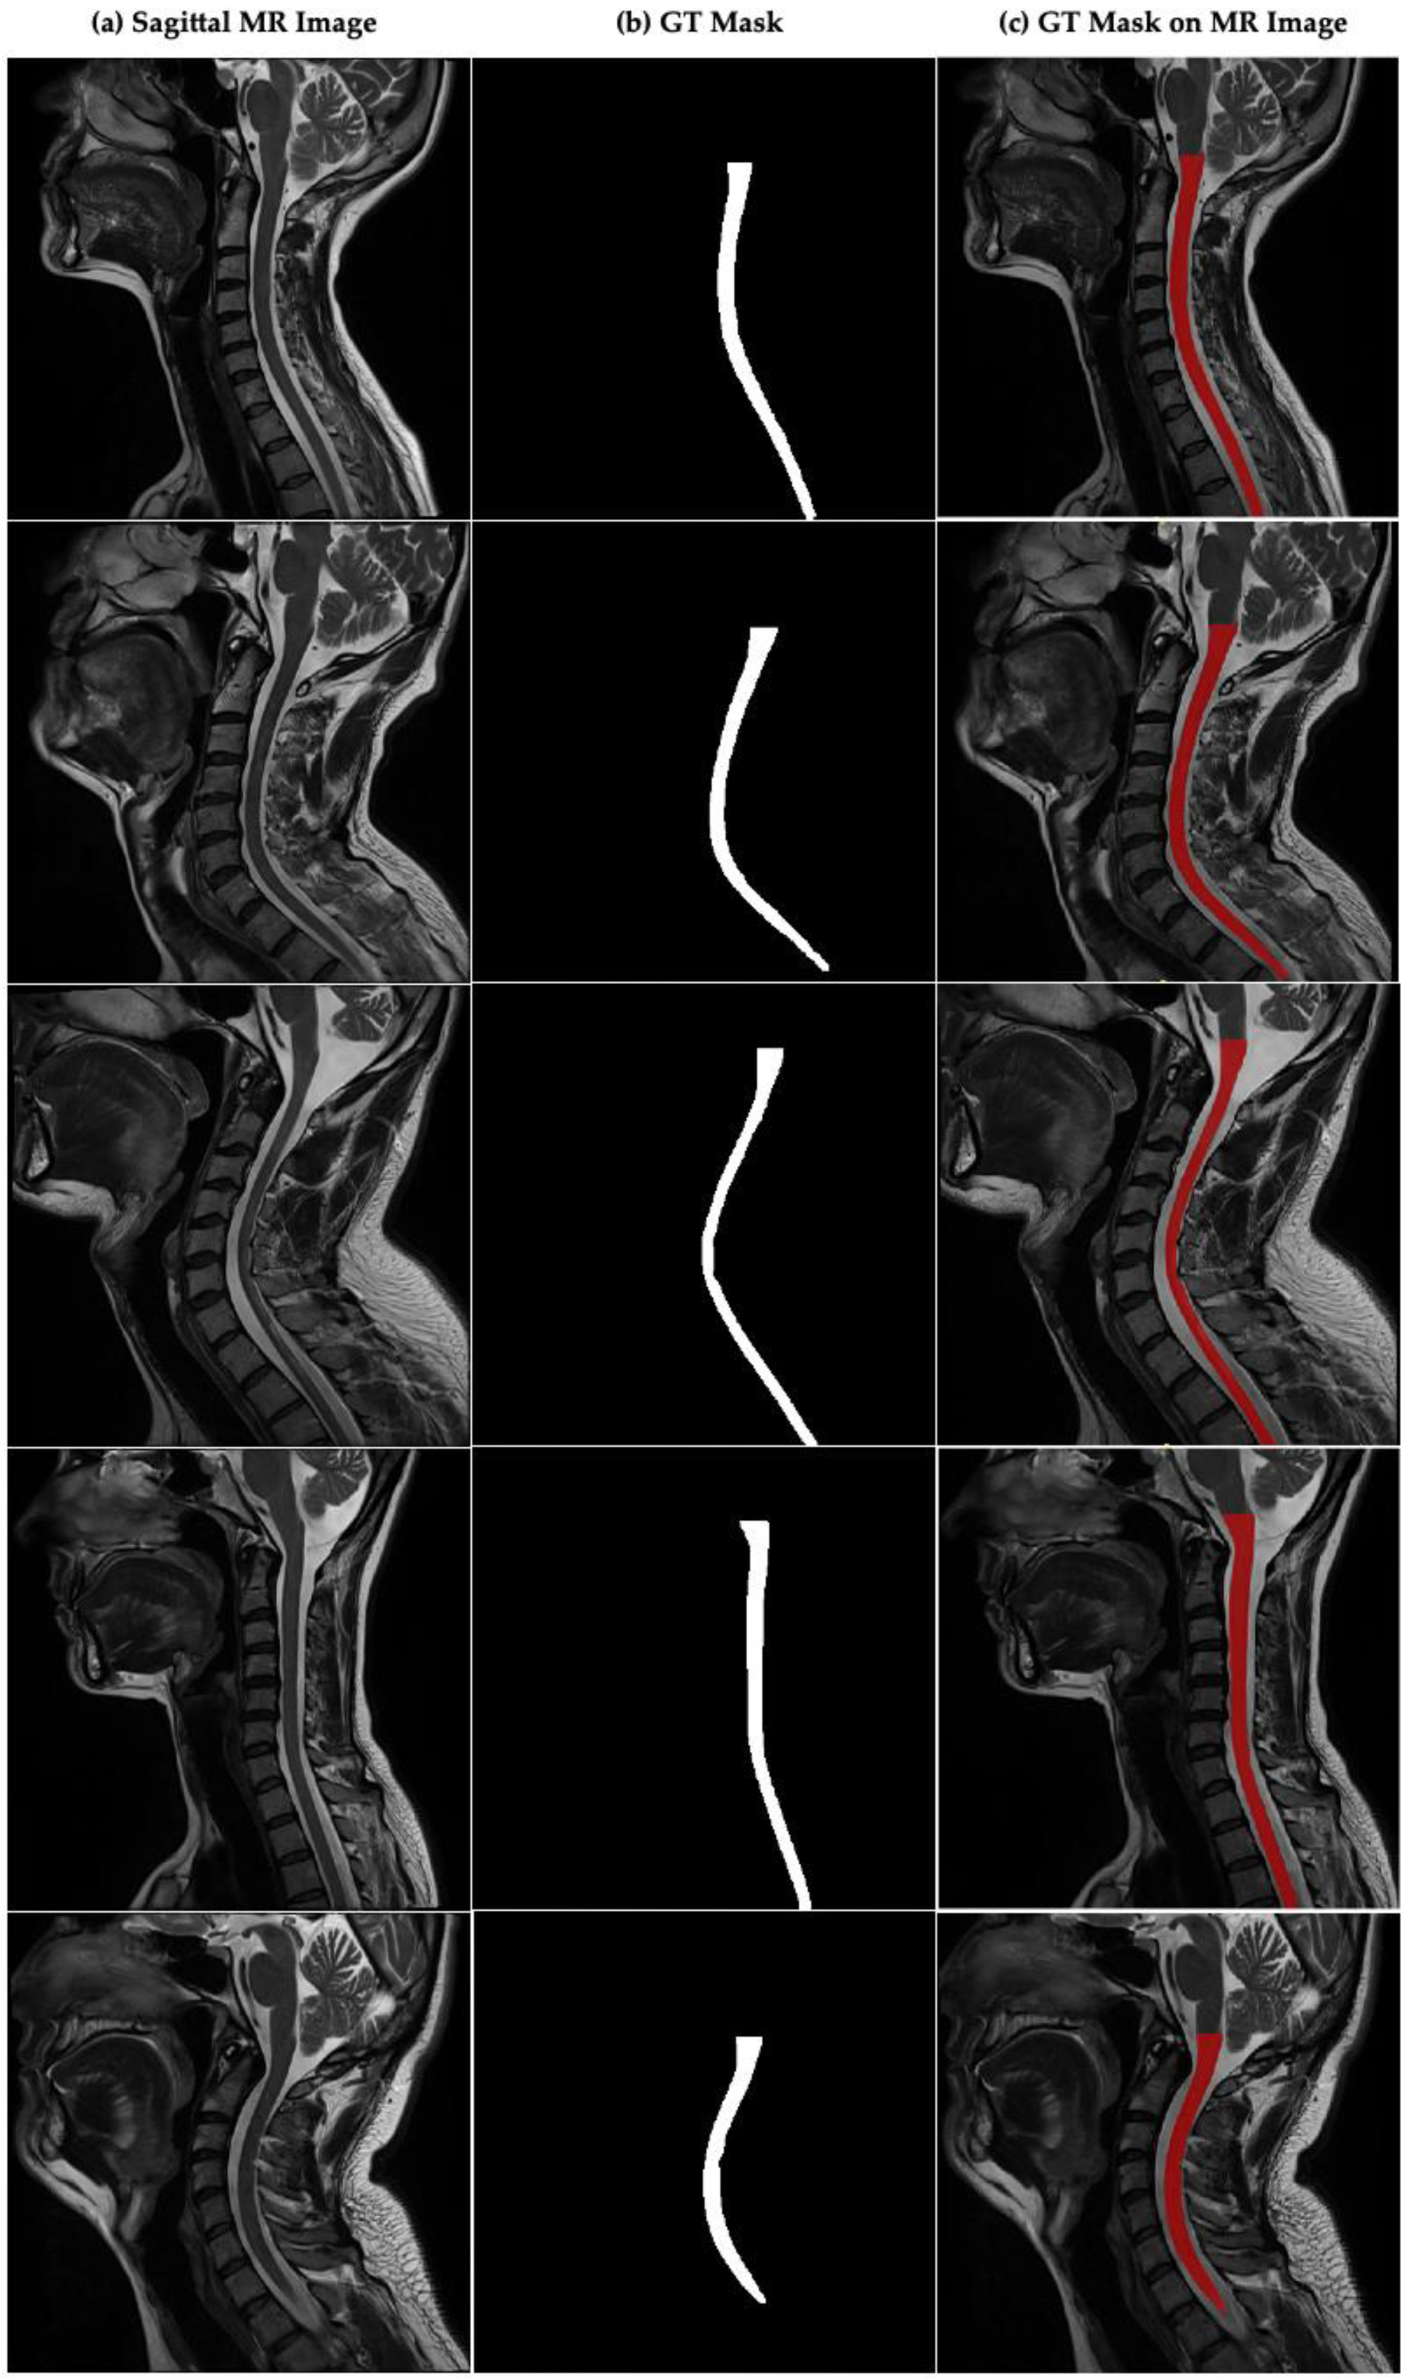

Figure 2a–c presents sample sagittal MR images of the cervical spinal region, the corresponding ground truth (GT) spinal cord segmentation masks that were manually annotated by expert radiologists, and the overlay visualizations of these masks on the original MR images. The image shows the expert-annotated ground truth masks for each image and illustrates the overlay of these masks on their respective MR images for visual validation. The masks are highlighted in red to clearly indicate the location and boundaries of the spinal cord.

Figure 2. Sagittal plane MR image of the cervical spinal cord and CSA boundaries annotated by the experts in cervical spinal cord. (a) Sagittal MR images in dataset, (b) GT mask annotated by experts for cervical spinal cord, (c) GT mask of CSA on sagittal MR image.